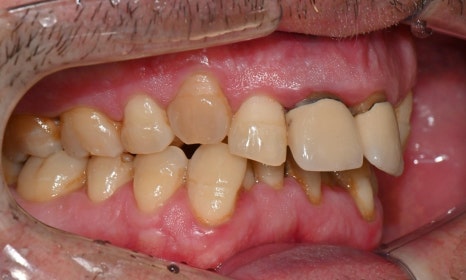

이 환자분은 영국에서 오신 40대 초반 남성분으로, 선천적으로 턱이 작아 어린 시절 턱을 앞으로 이동시키는 악교정 수술과 함께 약 6년 간 치아 교정을 받으셨다고 하셨습니다. 그러나 교정 치료가 충분히 만족스럽게 이루어지지 않았고, 이후 사고로 앞니를 다쳐 보철 치료를 받게 되었습니다. 시간이 지나면서 잇몸이 퇴축되어 앞니 보철물의 금속 부분이 노출되었으며, 제 2급 부정교합 및 불규칙한 치아 배열로 인해 심미적으로 정돈되지 못한 상태로 오랜 기간 지내오셨습니다. 이제는 앞니를 보다 아름답게 개선하고 싶다는 바람으로, 멀리 영국에서 한국까지 내원해 주셨습니다.

진단 결과, 교합시 하악 전치가 거의 보이지 않을 정도로 깊은 교합을 보이고 있었으며, 어린 시절 외상을 입었던 앞니는 치아 뿌리 부근에 광범위한 염증이 관찰되어 장기적인 유지가 어려운 상태였습니다. 이에 앞니 두 개는 발치를 결정하였고, 환자의 비교적 젊은 나이를 고려하여 가능한 한 최대한 치아를 보존하기 위해 앞니 부위 임플란트를 고려했습니다. 그러나 해당 부위 골 손실이 매우 심했고, 외국인 환자로 장기간 내원이 어려운 상황이었기 때문에, 광범위한 골이식을 동반한 임플란트 치료 보다는 비교적 짧은 기간 내에 기능과 심미를 회복할 수 있는 브릿지 보철 치료를 계획하였습니다.

치료가 모두 마무리된 후, 환자분의 미소는 이전과 비교해 전반적으로 한층 더 안정적이고 조화로운 인상으로 개선되었습니다. 앞니의 길이, 형태, 배열이 아랫입술 곡선을 따라 형성되는 smile arc와 자연스럽게 조화를 이루면서, 웃을 때 과도한 긴장감 없이 부드러운 심미적 균형을 회복할 수 있었습니다. 기능적인 교합 안정성과 함께 심미적인 만족도 역시 높게 나타났으며, 환자분도 결과에 대해 매우 만족해하셨습니다.